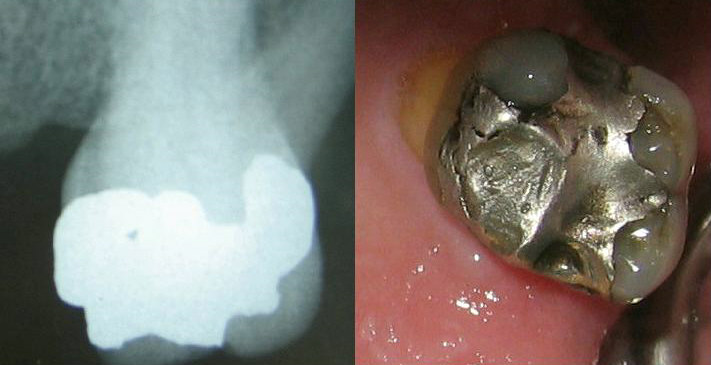

Dental amalgam

One material that I noted which didn’t make the regulatory list of hazardous implants but perhaps should is the mercury in dental amalgam. As the health of the population improves, increasing numbers of people are dying with their teeth intact (albeit repaired). Cremating dental amalgam releases mercury into the atmosphere causing environmental harm and potentially very serious health problems. The level of mercury in the hair of crematoria staff has been noted to be significantly higher than controls. The cost of reducing mercury emissions is considerable and the cost of installing filters in a crematorium is being passed on to the family of the deceased.

Image from: https://commons.wikimedia.org/wiki/File:Complex-amalgam.jpg